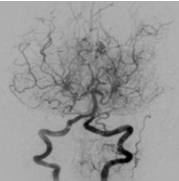

모야모야병은 뇌혈관이 서서히 좁아지며 막히는 희귀한 뇌혈관 질환으로, 뇌에 혈액 공급이 부족해지는 심각한 상태를 초래합니다. 이 질환은 일본어 "모야모야"에서 유래했는데, 이는 "연기가 피어오르는 모양"을 뜻합니다.

뇌혈관 조영술에서 좁아진 혈관 주변에 작은 측부 혈관들이 마치 연기처럼 보이는 모습이 특징이기 때문입니다. 주로 한국, 일본 등 동아시아에서 발병률이 높으며, 소아와 성인 모두에게 영향을 미치는 질환입니다. 소아에게는 뇌허혈이나 뇌경색으로, 성인에게는 뇌출혈로 나타나는 경우가 많아 나이에 따라 증상이 다르게 나타나는 점이 특징입니다.

모야모야병은 MRI, MRA(자기공명 혈관조영술), 뇌혈관 조영술, SPECT 같은 검사로 진단합니다. 이 검사들은 단순히 질환을 확인하는 데 그치지 않고, 병의 진행 정도와 수술 필요성을 판단하는 데도 사용됩니다. 현재 모야모야병은 불치병으로 분류되며, 근본적인 치료법은 없지만 증상을 완화하고 합병증을 예방하는 치료는 가능합니다.